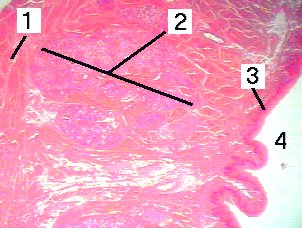

This is a very low magnification of a section throug the tongue.

Fig 3 1. Skeletal muscle

2. Mixed glands of Nuhn

3. Unkeratinized stratified squamous epithelium

4. Inferior surface